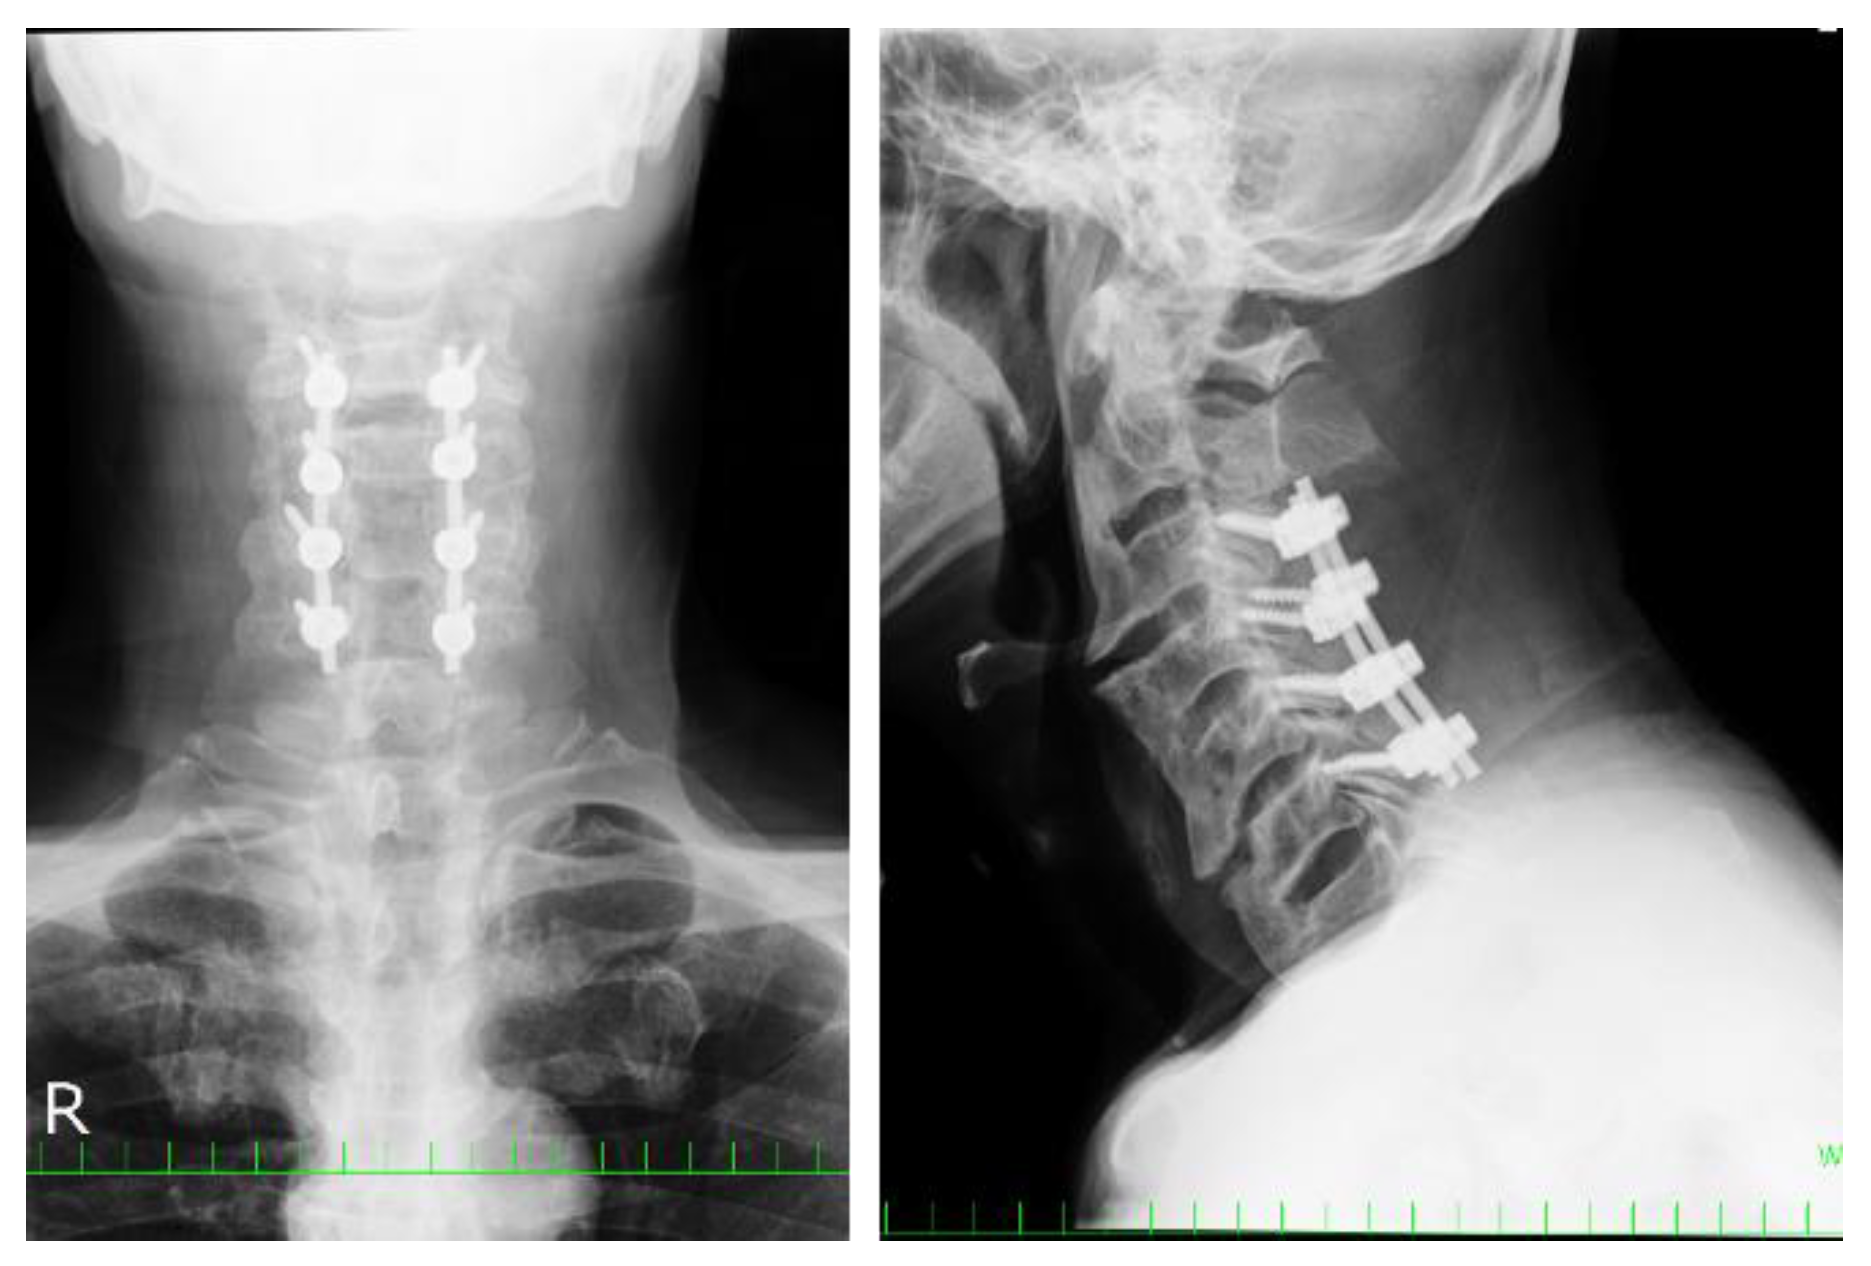

2.5. Clinical Presentations